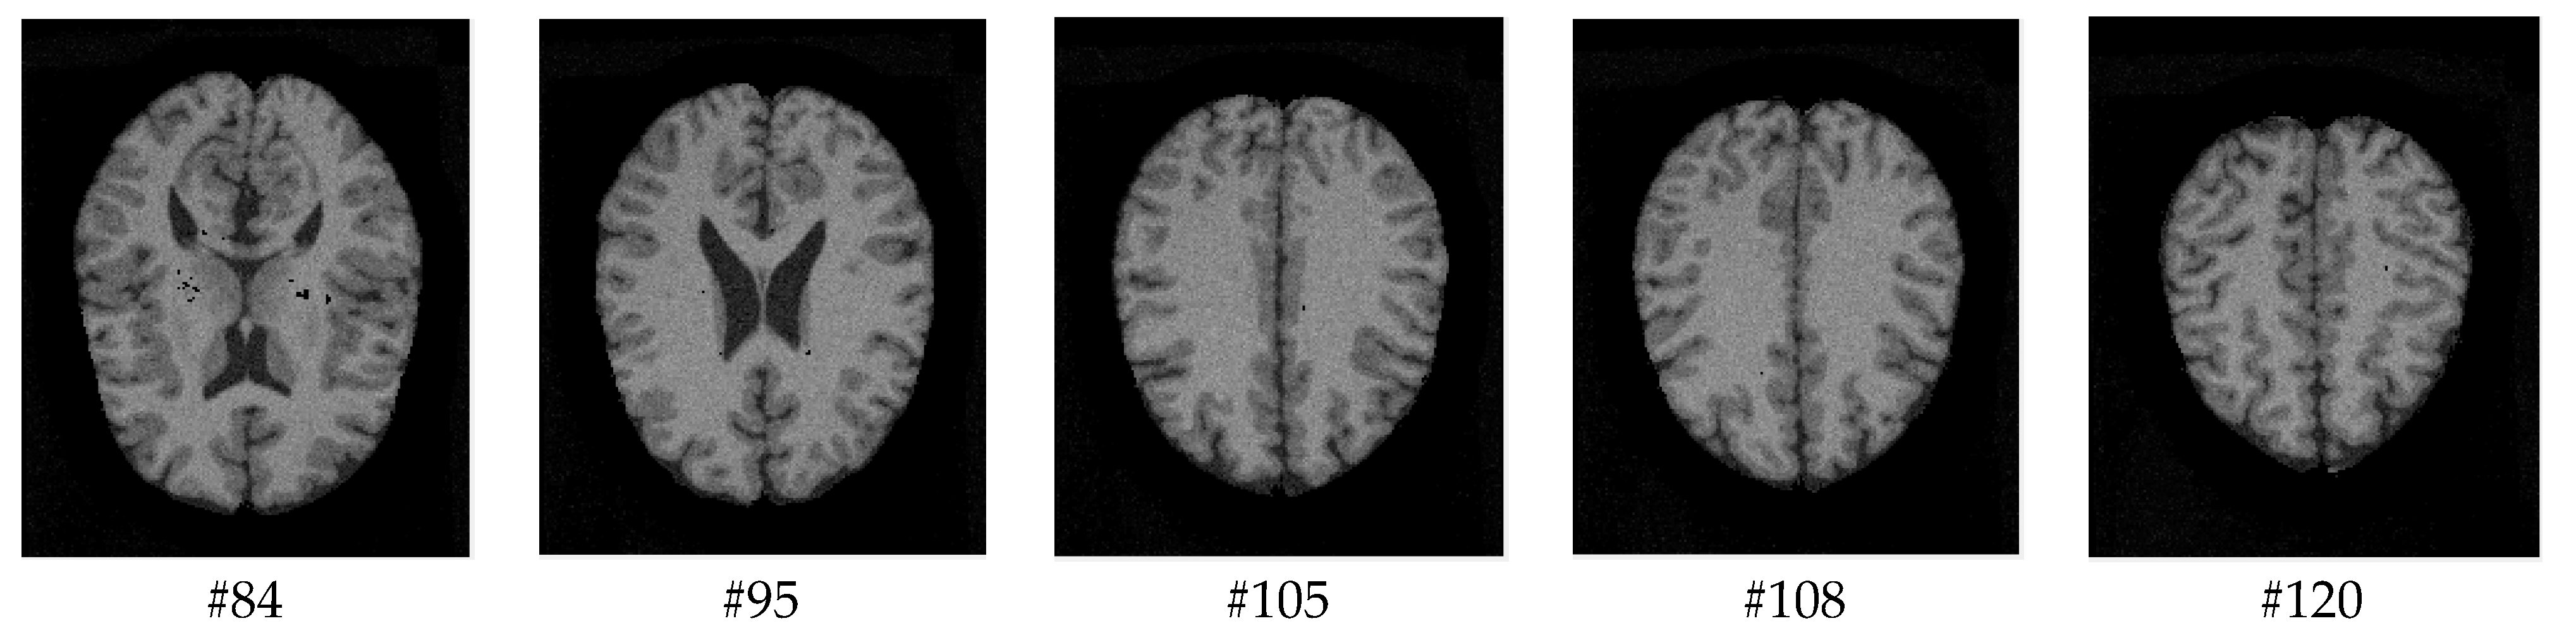

As mentioned before, the images of the first five datasets in Table 3 were used to evaluate the performance of the HMRF-WOA. Figure 1, Figure 2, Figure 3, Figure 4 and Figure 5 show some slices of a T1-weighted image (slices: 84, 95, 105, 108, 120). These brain images correspond to the slices under different types of conditions, such as database type, dimension image, noise level, intensity non-uniformity level, and slice thickness (mm). In Table 1, rows 1 to 5 summarize the parameters of Figure 1, Figure 2, Figure 3, Figure 4 and Figure 5, respectively. Figure 6 represents the ground truth segmentation of slices 84, 95, 105, 108, and 120. In this figure, each column contains the three tissues, GM, WM, and CSF, of each slice. Figure 7, Figure 8, Figure 9, Figure 10 and Figure 11 show the segmentation results, where the four tissues (BG, GM, WM, and CSF) are shown with different colors. The yellow, red, and green colors represent the segmented regions of GM, WM, and CSF, respectively. As we can also see from these figures, the resulting segmented images in Figure 7, Figure 8, Figure 9, Figure 10 and Figure 11 are almost close to the initial images in Figure 1, Figure 2, Figure 3, Figure 4 and Figure 5.

The qualitative analysis provides a visual representation of the segmentation approaches. The visual comparison of the resulting images using the HMRF-WOA appears to be more similar to the reference image (ground truth), where Figure 1, Figure 2, Figure 3, Figure 4 and Figure 5 show the GM, WM, and CSF tissue regions of the reference image with higher values of noise levels (3, 5, 7, and 9%) and intensity non-uniformity levels (20, 40%), whereas Figure 7, Figure 8, Figure 9, Figure 10 and Figure 11 show the subject images obtained using the proposed technique. However, this result shows that with higher values of noise and intensity non-uniformity, the algorithm, with its hyperparameters, is able to segment the tissue regions correctly.

Figure 3. Slices with Noise = 5%, INU = 20% of database 3.

Figure 9. Segmentation results of the images illustrated in Figure 3.